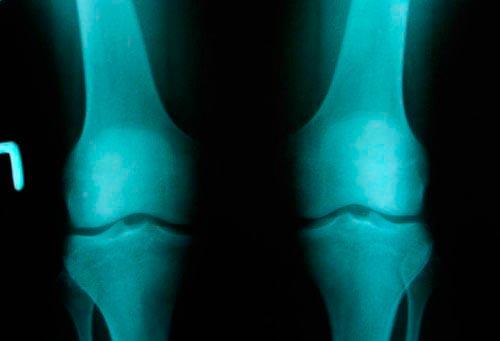

Артроз колена. Артроз коленного сустава

Артроз коленного сустава (гонартроз) – это хроническое дегенеративно-дистрофическое заболевание коленного сустава, которое характеризуется разрушением суставных хрящей, деформацией коленного сустава с последующим ограничением движений в нем.

Разрушение хряща при артрозе коленного сустава

Артроз коленного сустава занимает первое место по распространенности в общей структуре. Заболеванию подвержены в основном лица старше сорока лет – в данной возрастной группе артроз коленного сустава чаще встречается у женщин, среди пациентов более молодого возраста преобладают лица мужского пола. Примерно в 6-7% случаев артроз коленного сустава приводит к инвалидности.

Коленный сустав образуется суставными поверхностями бедренной и большеберцовой кости. Передняя поверхность коленного сустава защищена надколенником (коленной чашечкой). Суставные поверхности бедренной и большеберцовой кости, как и задняя поверхность надколенника, покрыты плотноэластичным гиалиновым хрящом, толщина которого составляет 5-6 мм. При ударных нагрузках хрящ выполняет амортизирующую функцию, а при движениях уменьшает трение. У клинически здоровых людей процессы синтеза и разрушения хрящевой ткани находятся в равновесии, когда равновесие нарушается в сторону увеличения деструкции, развивается артроз. При артрозе коленного сустава в мелких внутрикостных кровеносных сосудах, питающих гиалиновый хрящ, нарушается кровообращение, вследствие чего поверхность хряща становится более сухой, а со временем утрачивает гладкость. На поверхности гиалинового хряща образуются трещины, что служит причиной регулярного микротравмирования хряща при движении. С прогрессированием патологического процесса хрящевая ткань истончается, суставная площадка расплющивается, адаптируясь к нагрузке. По краям суставных поверхностей возникают остеофиты, которые представляют собой костные выросты, формирующиеся по причине компенсаторного разрастания костной ткани. Патологический процесс захватывает синовиальную оболочку и капсулу сустава. Суставная жидкость становится более вязкой, хуже выполняет свои функции, что приводит к усилению деструктивных процессов в суставе. При дальнейшем прогрессировании заболевания хрящ истончается еще больше, на некоторых участках исчезает вовсе. Это приводит к резкому усилению трения между суставными поверхностями и деформации костей, образующих сустав. Коленный сустав деформируется, деформация может быть вальгусной, т. е. Х-образной, или варусной, т. е. О-образной. Движение в пораженном суставе ограничивается вплоть до полного исчезновения (формируется– необратимое и полное разрушение сустава).